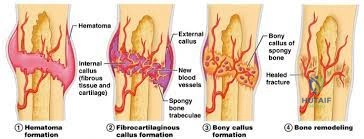

In this comprehensive guide, we discuss everything you need to know about Fracture Healing Understanding: How Bones Repair & What Treatments Help. Fracture healing understanding involves a complex, sequential process restoring injured bone. It progresses through stages: inflammation (hematoma formation, cytokine release from immune cells like macrophages, neutrophils, and platelets), followed by reparative phases. Healing type (primary via Haversian remodeling or secondary via endochondral ossification) is dictated by mechanical stability and strain at the fracture site.

Secondary (indirect) bone healing is the natural physiological pathway and occurs under conditions of relative stability (strain between two and ten percent). This is seen with conservative management (casting, bracing) or flexible surgical constructs (intramedullary nails, bridge plates, external fixators). Secondary healing progresses through four overlapping phases. The initial inflammatory phase involves hematoma formation, macrophage infiltration, and the release of osteoinductive cytokines (Interleukin-1, Interleukin-6, Tumor Necrosis Factor-alpha). This is followed by the soft callus phase, characterized by chondrogenesis and the formation of a cartilaginous scaffold. The hard callus phase involves endochondral ossification, where the cartilage is mineralized and replaced by woven bone. Finally, the remodeling phase, governed by Wolff's Law, converts the woven bone into mature lamellar bone oriented along the lines of mechanical stress.